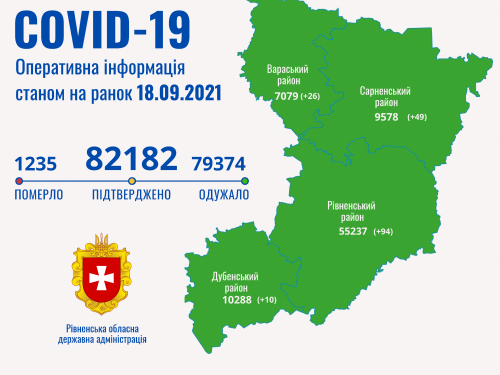

Пів тисячі - у важкому стані, 9 жителів Рівненщини померли за добу від коронавірусу